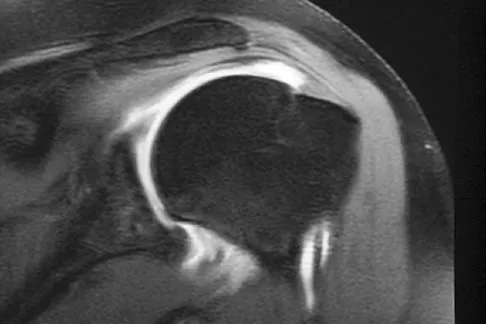

Figures 36a and 36b show the MRI scans of a patient who has shoulder weakness. What is the most likely diagnosis?

Explanation